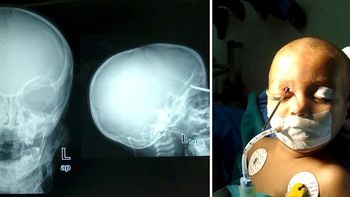

Un niño catamarqueño pasó casi un mes con un alfiler de gancho incrustado en su garganta porque los distintos médicos que lo atendieron en la localidad catamarqueña de Rincón no lo habían detectado, tras lo cual fue operado con éxito en Córdoba.

El bebe fue operado en los últimos días en una clínica de Córdoba donde le extrajeron el objeto metálico.

Así, la familia viajó de urgencia a la ciudad de Catamarca y en una clínica le colocaron una sonda con cámara que localizó el objeto metálico, tras lo cual fue derivado y operado en Córdoba.